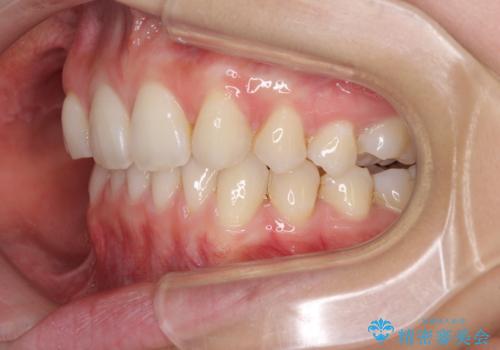

上顎前歯が2本欠損 インビザラインによる叢生の解消

- 深い咬み合わせと前歯のデコボコを気にして来院された患者様です。

上顎前歯2本が欠損しているため、妥協的なゴールを設定しインビザラインで矯正治療を行うこととしました。

上下前歯の大きさのアンバランスにより、深い咬み合わせと奥歯の咬みにくさがなかなか解決されず、治療に長期間を要することとなりました。